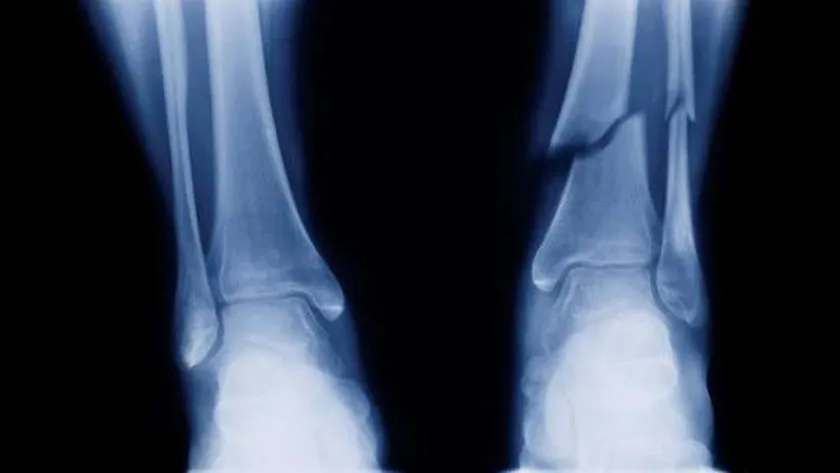

«القومي للبحوث» يحذر من عدوى بكتيرية عند تركيب شرائح معدنية لعلاج الكسور

قالت الدكتورة زينب محمد، باحثة بقسم الحراريات والسيراميك ومواد البناء بالمركز القومي للبحوث، إن عملية تركيب الشرائح المعدنية لعلاج كسور العظام قد يصحبها عدوى بكتيرية، وهذا ويتطلب إعطاء المريض كميات كبيرة من المضادات الحيوية بشكل دوري ولفترات طويلة، وقد تفشل هذه الطريقة في القضاء على البكتيريا بشكل كامل داخل الجسم، لذلك يتم تحميل الطلاء بأدوية مضادة للبكتيريا مثل المضادات الحيوية.

وأوضحت أن المواد الحيوية بشكل عام والمواد المستخدمة في علاج أمراض العظام بشكل خاص لها أهمية كبيرة في التطبيقات الطبية وتطورت هذه المواد كثيراً على مدى نصف قرن مضى، خاصة المواد المستخدمة فى علاج أمراض العظام مثل الكسور الناتجة من الحوادث وخلايا العظام التالفة نتيجة لكبر السن، مؤكدة أنه يجب أن تتميز هذه المواد بأن تكون متلائمة مع الجسم لكى تبقى لفترات طويلة داخله حتى لا يتم مراجعتها جراحياً.

ونوهت إلى أن السبائك الفلزية، مثل سبائك التيتانيوم والحديد المقاوم للصدأ والكوبالت تعتبر من أكثر المواد المستخدمة في جراحات العظام والمفاصل وتتميز هذه السبائك بقدرتها العالية على مقاومتها للتآكل، وكذلك خواصها الميكانيكية العالية وتُصنف هذه المواد من مفهوم المواد الحيوية على أنها مواد خاملة حيوياً، حيث أنها لا تتفاعل كميائيا مع الأنسجة الحية داخل الجسم، فهي لا تلتصق بالعظام وتُكوّن كبسولات ليفية حولها ويؤدي ذلك إلى انفصال السبيكة المنزرعة في الجسم بعد فترة من زرعها فلا تؤدي الغرض المطلوب منها.